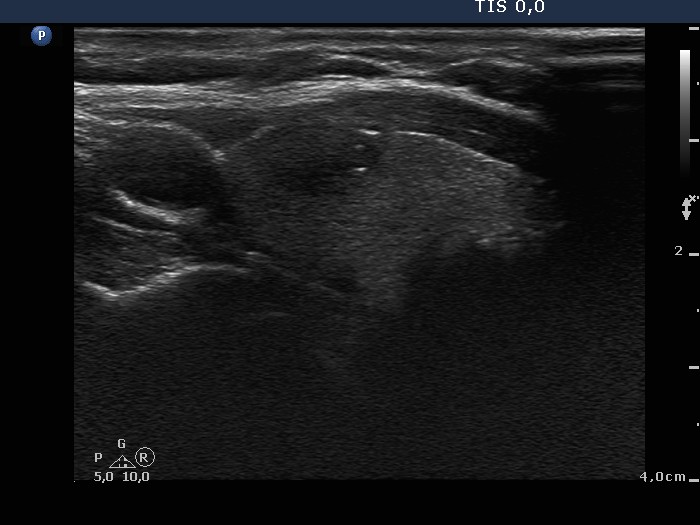

The borders of the nodule - case 638 |

Clinical presentation: A 68-year-old woman was referred for evaluation of a nodule discovered on neck ultrasonography. She was treated for breast cancer, which gave metastasis to the lung.

Ultrasonography. There was a hypoechogenic nodule with cotton-like hyperechogenic patches and smaller punctate hyperechogenic granules in the right lobe. The nodule presented intranodular blood flow and lobulated margins.

Cytological diagnosis: suspicion of medullary carcinoma.

Histopathology: medullary carcinoma

Comment. The tumor presents lobulated margins.